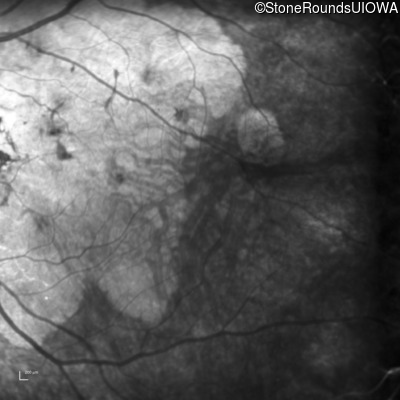

Infrared Fundus Photograph - Right - 20/25 -2

Exemplar